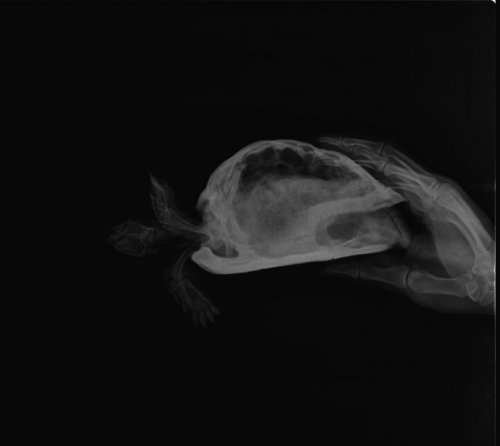

Podolnyi Ваше имя: Подольный Константин Локация: Украина, Днепр Опубликовано: 7 октября 2020 Опубликовано: 7 октября 2020 У всех трёх, согласно рентгену - нарушена минерализация костных структур. У первой черепахи это видно в поясничном отделе позвоночника (идёт позвоночник с четкой картинкой и после размывается), у второй черепахи весь позвоночный стол уже затронут. третья черепах, более интересный пациент. У неё также затронут весь позвоночный столб и ко всему-же был перелом позвоночника. Был он, скорее всего, за счёт метаболических нарушений. По поводу «клапанов», нет у рептилий никаких клапанов. У черепахи есть патология дыхательной системы: на легочном поле есть выраженный фиброзный процесс с образованием отдельных полостей, которые все же участвуют в акте дыхания. клиника дыхательной недостаточности есть ? Ей можно сдать общий анализ крови. И всем черепахам пройти курс элеовита и кальция глюконата. И на будущее 2 раза в год это делать. Кормить их раз в 3 дня, на 30 минут ставите еду и сколько съедят - после убираете остаток. Иногда, пропускать 1 кормление, т.е. раз в 6 дней кормёжка.

victoria146 Ваше имя: Виктория Локация: Воронеж Опубликовано: 11 октября 2020 Автор Опубликовано: 11 октября 2020 @moth это важное уточнение, спасибо! Так эти травы будут полезны? Хотелось бы у спецов узнать про магний. Как часто можно добавлять кальций+магний, потому как Аркадия заявляет что согласно последним исследованиям магний очень важен для рептилий.